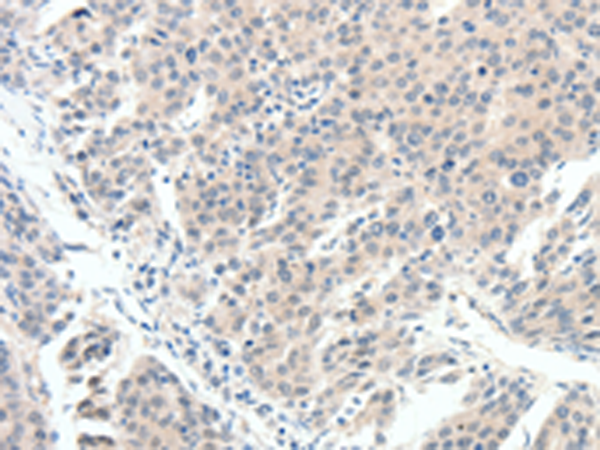

分类: 科研抗体货号: P11340别名:应用: IHC反应种属: Human, Mouse, Rat